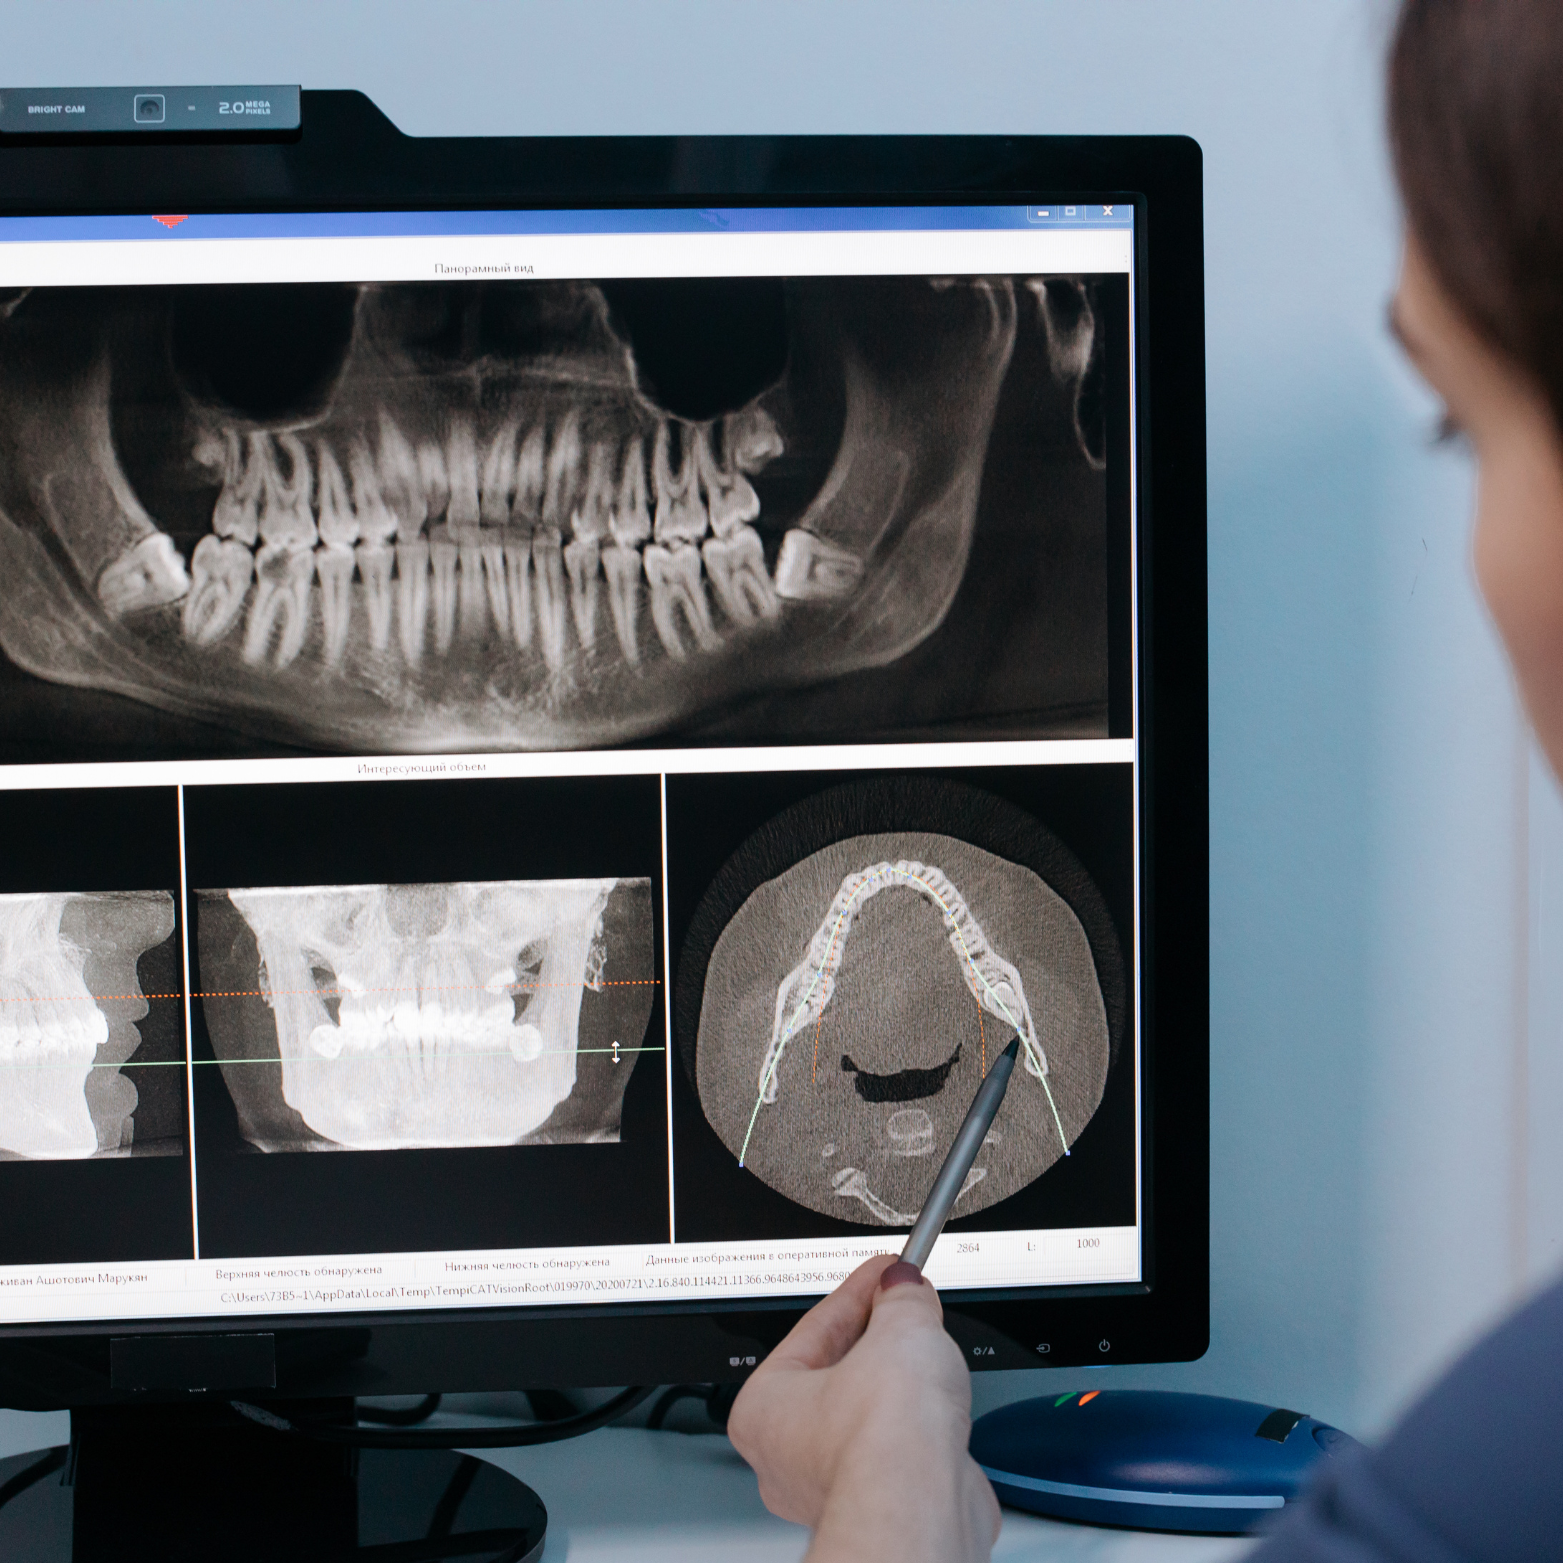

CBCT (3D X-RAY)

3D imaging in dental X‑ray is essential for complex cases such as root canal treatments, implant placements, and others oral surgeries because it reveals detailed views of the tooth, bone, and surrounding structures that conventional 2D images can miss. By visualizing canal anatomy, bone density, proximity to nerves and sinuses, and the true extent of pathology, clinicians can plan procedures more precisely, anticipate potential complications, choose the most appropriate instruments and approaches.

We believe complex cases demand greater detail to support confident decision‑making, reduce intra-operative surprises, and achieve safer, more predictable outcomes with fewer complications.